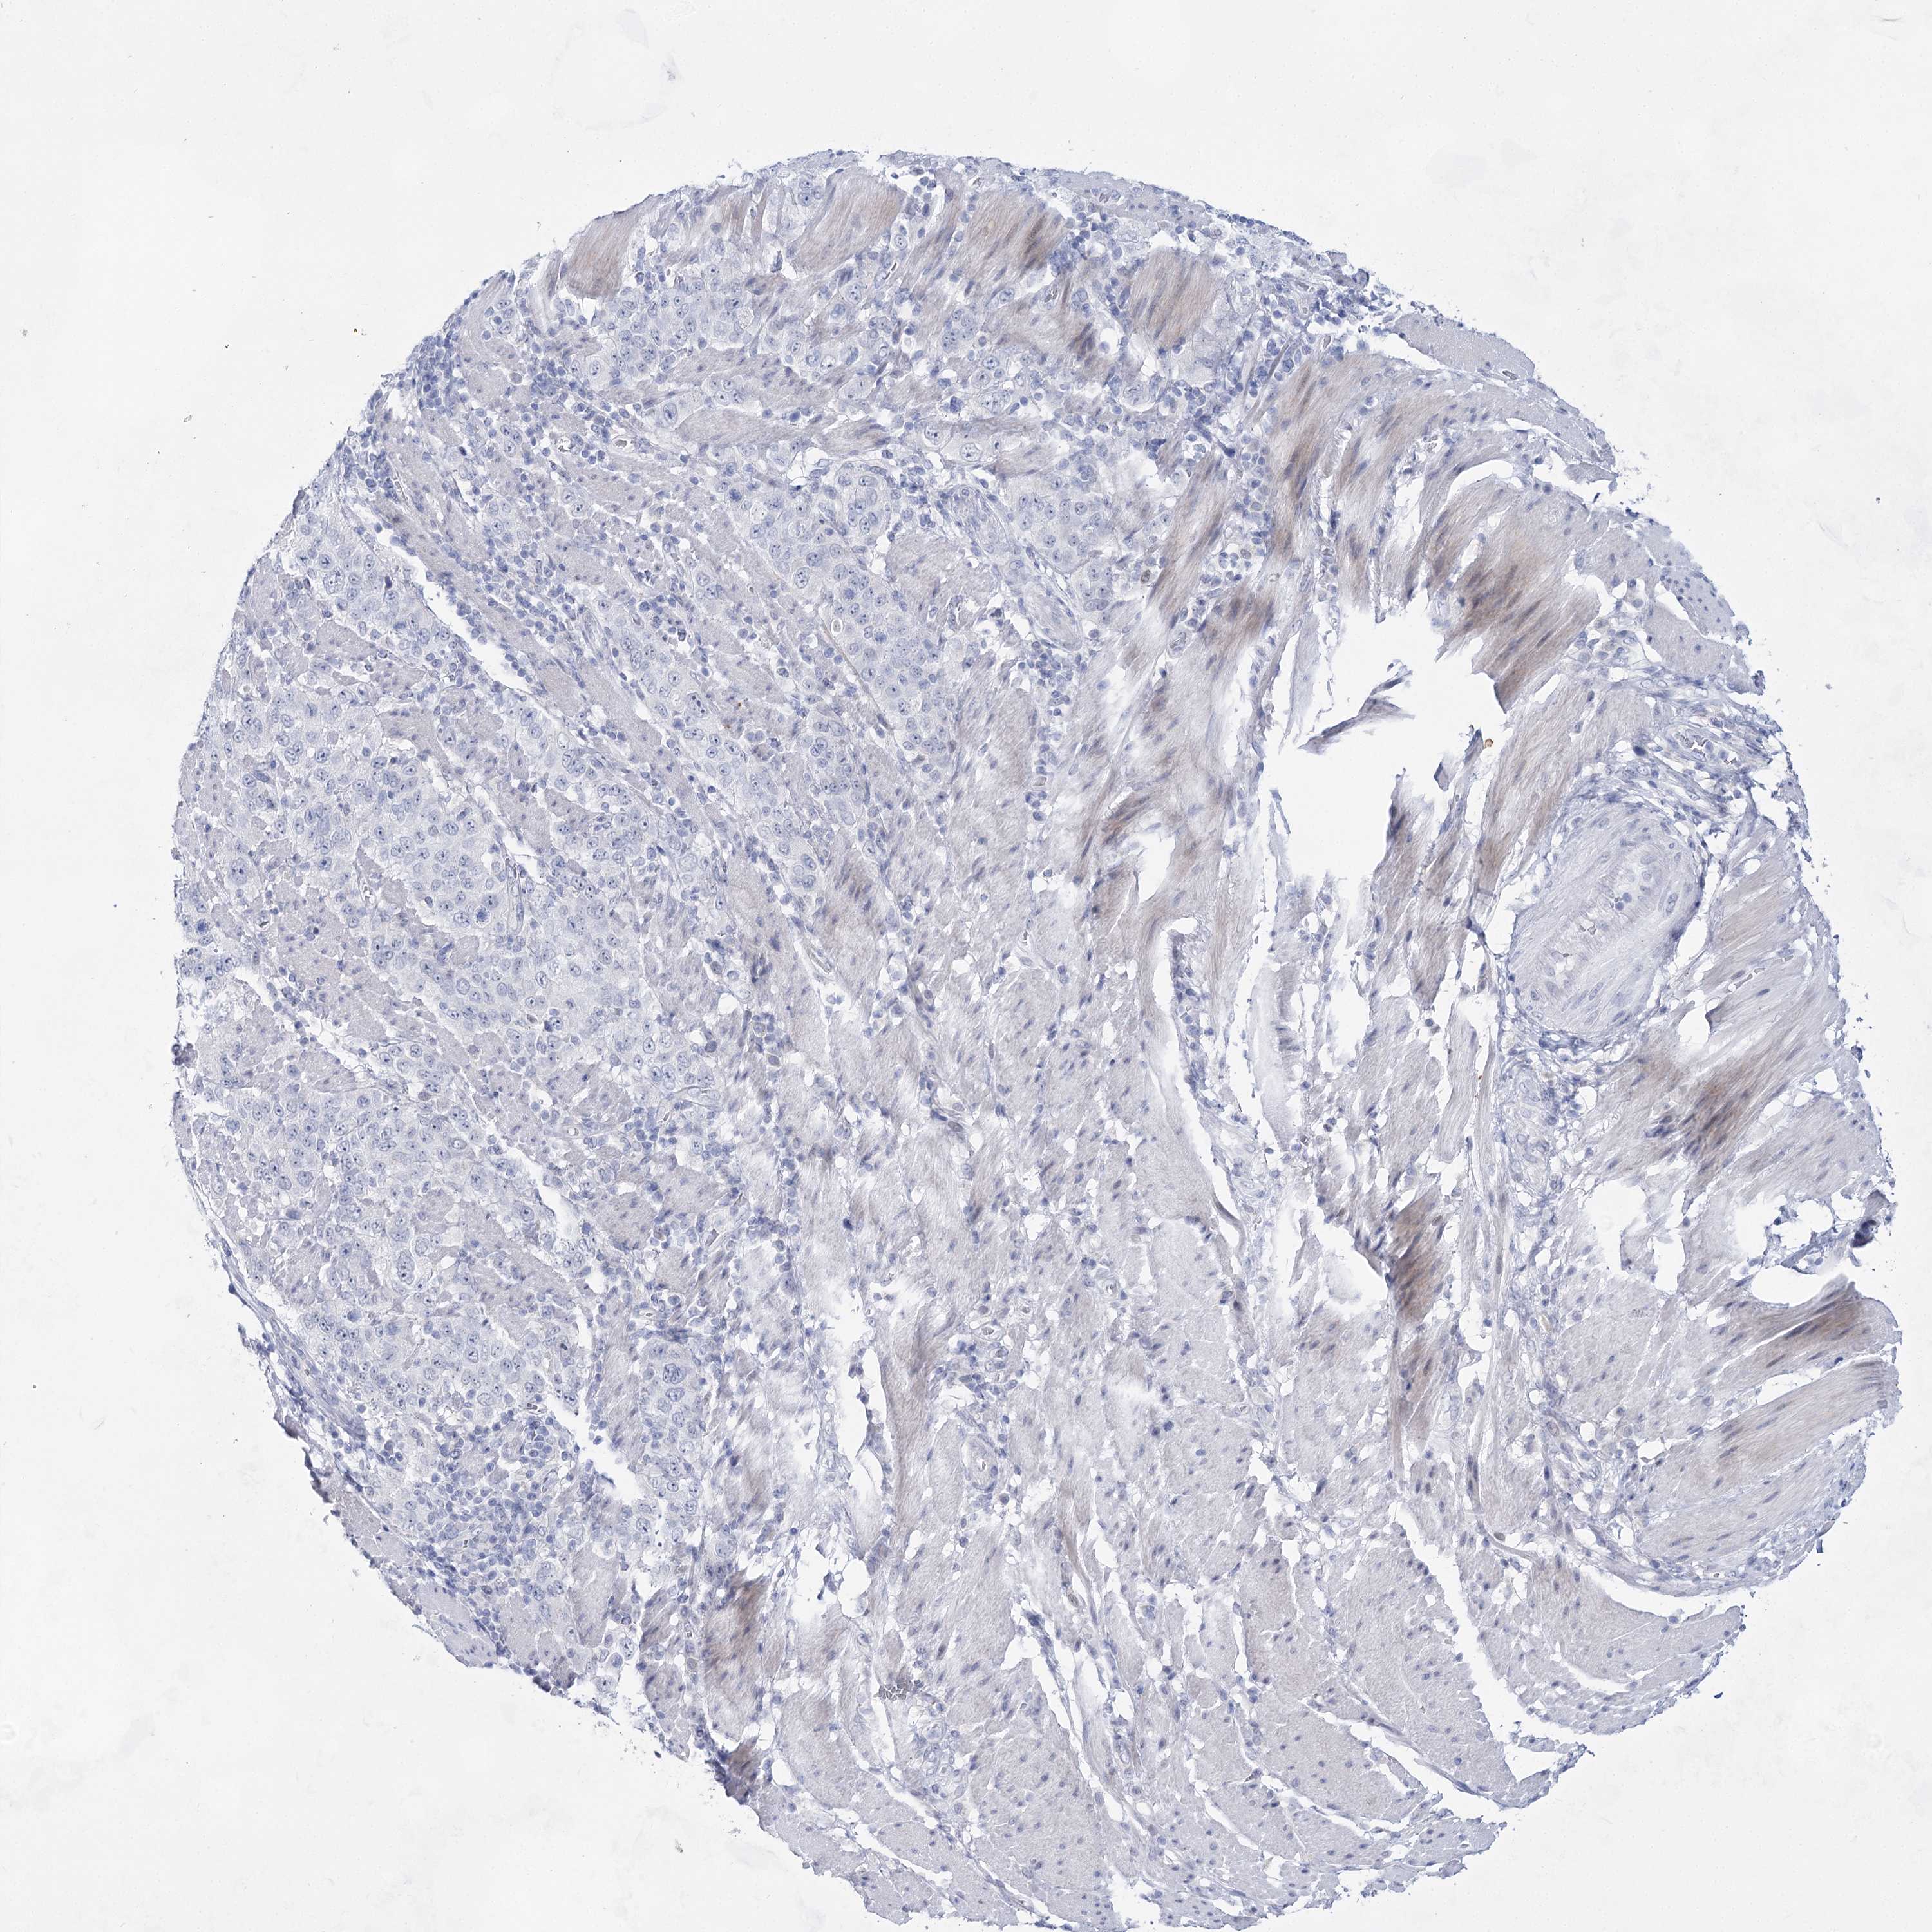

STOMACH CANCER - Protein expressioni

A mouse-over function shows sample information and annotation data. Click on an image to view it in a full screen mode. Samples can be filtered based on level of antibody staining by selecting one or several of the following categories: high, medium, low and not detected. The assay and annotation is described here.

Note that samples used for immunohistochemistry by the Human Protein Atlas do not correspond to samples in the TCGA dataset.

Antibody stainingi

Antibody staining in the annotated cell types in the current human tissue is reported as not detected, low, medium, or high, based on conventional immunohistochemistry profiling in selected tissues. This score is based on the combination of the staining intensity and fraction of stained cells.

Each image is clickable and will lead to virtual microscopy that enables deeper exploration of all samples and also displays staining intensity scores, fraction scores and subcellular localization as well as patient and tissue information for each sample.

Antibody HPA036752

Antibody HPA036753

Staining

High

Medium

Low

Not detected

Intensity

Strong

Moderate

Weak

Negative

Quantity

>75%

75%-25%

<25%

None

Location

Nuclear

Cytoplasmic/membranous

Cytoplasmic/membranous,nuclear

Adenocarcinoma, NOS